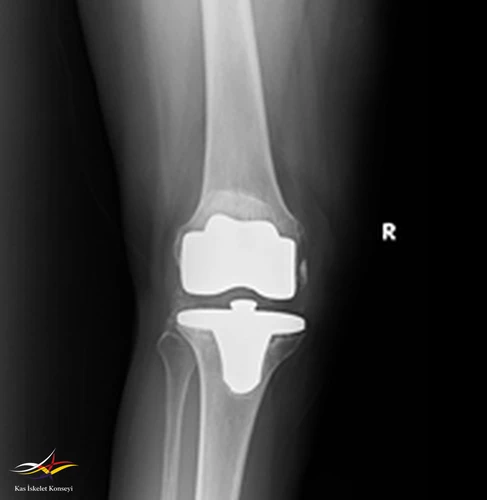

Resim 1. Revizyon ameliyatı öncesi AP direkt grafi.